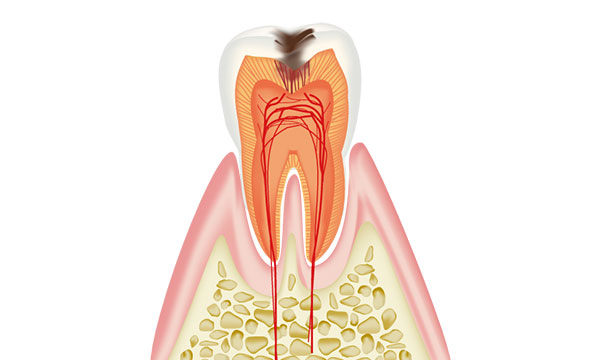

虫歯は進行の程度で5段階に分けられます。

虫歯が象牙質の中でさらに進行し、歯の神経がある空間に達した状態です。 神経が細菌感染をおこし、激しい痛みがでます。激しい痛みによって頭痛を引き起こすこともあります。 主な症状は何もしていなくてもズキズキとした脈打つような激痛がでたり、温かいもので痛みが増し、冷やすと落ち着いたりします。 虫歯がここまで進行すると歯を残す為に神経を取る治療が必要です。